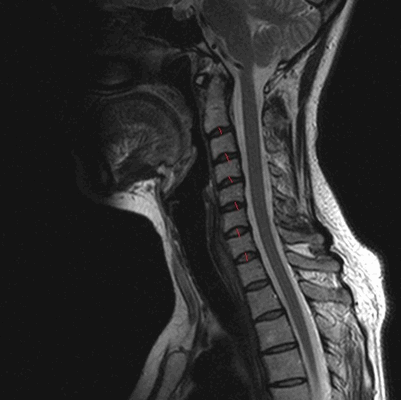

МРТ позвоночника в шейном отделе, оценка высоты дисков (указана красными линиями)

На сериях МРТ, выполненных в аксиальной, корональной и сагиттальной плоскостях, взвешенных по Т2-ВИ, Т1-ВИ и STIR-ИП, получены изображения шейного отдела позвоночника.

Определяется патологический кифоз с вершиной на уровне тел позвонков С5-С6.

Выявляются дегенеративно-дистрофические изменения в виде умеренно выраженного понижения интенсивности сигнала от межпозвонковых дисков в сегментах С2-Th1, со снижением высоты в сегментах С5-С7, а также формирования передних и заднебоковых краевых костных разрастаний. Унковертебральный артроз на уровне сегментов С5-С7.

В смежных отделах позвонков С6-С7 определяются зоны гиперинтенсивного МР-сигнала на Т2-ВИ, STIR-ИП и гипоинтенсивного в Т1-ВИ (вероятно, обусловленные отёком вещества костного мозга).

Определяются неровности смежных замыкательных пластин тел позвонков С5-С7 за счет хрящевых узлов Шморля.

В сегменте С3-С4 под краевыми остеофитами определяется дорзальная медианная протрузия межпозвонкового диска, размером до 2,5мм. Переднее субарахноидальное пространство деформировано. Межпозвонковые отверстия умеренно сужены, достоверных данных за компрессию корешков нервов не выявлено. Передне-задний размер позвоночного канала до 14мм.

В сегменте С5-С6 под краевыми остеофитами определяется задняя диффузная протрузия межпозвонкового диска, размером до 2,5мм. Переднее субарахноидальное пространство деформировано. Межпозвонковые отверстия умеренно сужены, достоверных данных за компрессию корешков нервов не выявлено. Передне-задний размер позвоночного канала до 13мм.

В сегменте С6-С7 под краевыми остеофитами определяется задняя диффузная протрузия межпозвонкового диска, размером до 2мм. Переднее субарахноидальное пространство деформировано. Межпозвонковые отверстия умеренно сужены, достоверных данных за компрессию корешков нервов не выявлено. Передне-задний размер позвоночного канала до 14мм.

Сигнальные характеристики от шейных позвонков не изменены.

Видимые отделы спинного мозга в размерах не увеличены, имеют четкие контуры и однородную структуру, интенсивность МР сигнала не изменена.

Паравертебральные мягкие ткани не изменены.

МР-признаки дегенеративно-дистрофических изменений шейного отдела позвоночника с нарушением статики. Протрузии дисков на уровне сегментов С3-С4, С5-С6, С6-С7. Унковертебральный артроз. Хрящевые узлы Шморля смежных замыкательных пластин тел позвонков С5-С7.